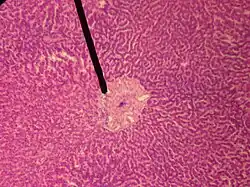

![]() A single lobule of the liver of a pig. X 60. (Central vein not labeled, though region is visible. Central vein would be a single vein at the center of the lobule.) | |

In microanatomy, the central vein of liver (or central venule)[1] is a vein at the center of each hepatic lobule.[2] It receives the blood mixed in the liver sinusoids to drain it into hepatic veins.[3]